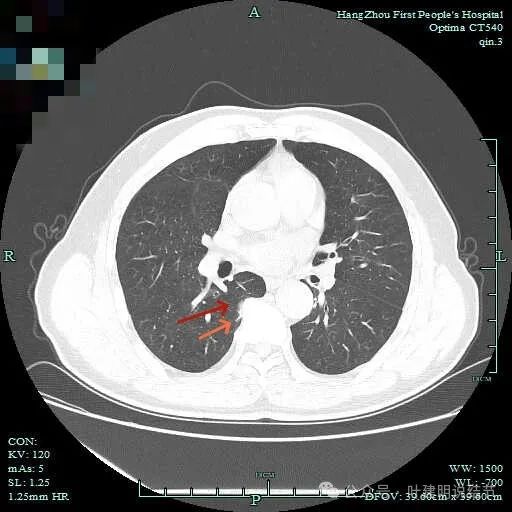

次病灶连续层面观察:

紧贴脊柱处混合密度,趴在脊柱上,这不像结节状。

但有小血管似的,磨玻璃部分界限较清。但此类异常影像在正常人的CT上也挺常见。

密度较高,确实像血管进入。但病灶片状,趴在脊柱上。

此层显得更呈小片状了。